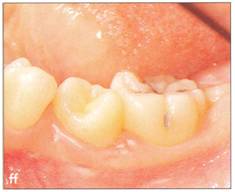

Fi 545e45f gs 5-3p and 5-3q One year 4 months after transplantation. |